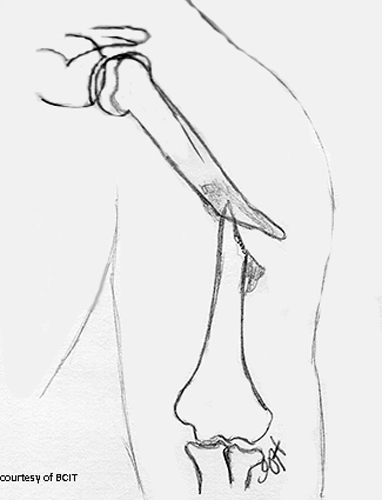

What nerve is at risk in humeral shaft fractures?

Radial nerve.

What type of forces cause different humeral fracture patterns?

Torsion = spiral, transverse = angled blow, high energy = comminuted.